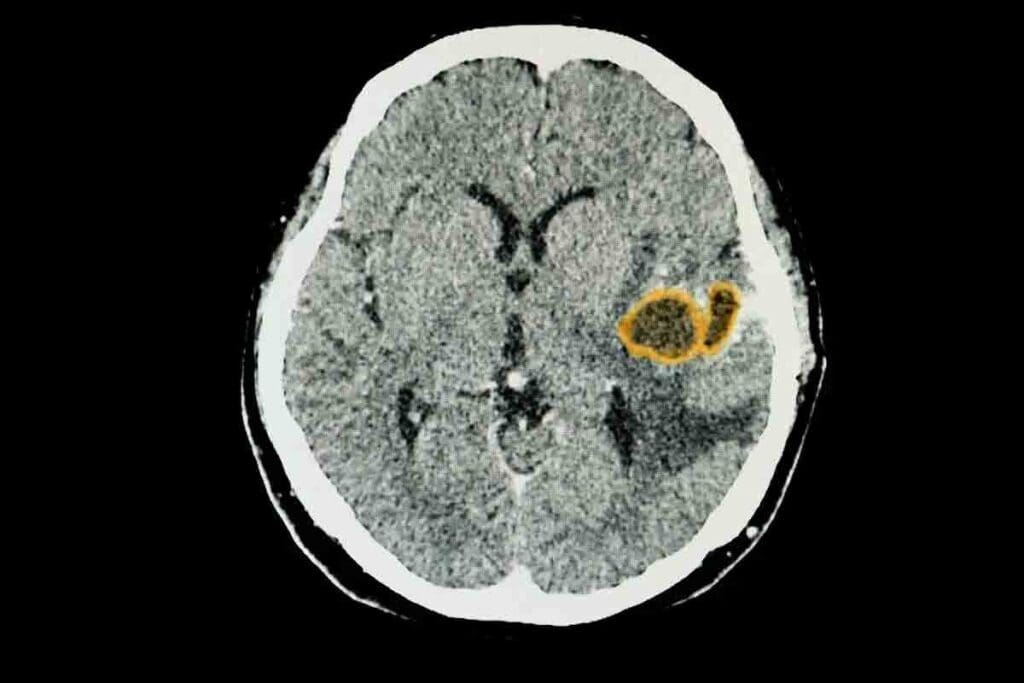

At Liv Hospital, we know how serious brainstem gliomas are for kids. These tumors grow in or near the brain. They can cause headaches and nausea by pressing on the brain.

Gliomas are common brain cancers in kids. Astrocytoma is one type that often occurs. It’s important to understand these conditions to help our young patients.

Gliomas in children are complex brain tumors. They come from the brain’s glial cells. These tumors can be different in how they act, making it key to understand how they grow.

Gliomas in children are divided based on the type of glial cell and the tumor’s growth. This helps doctors predict how the tumor will behave and choose the right treatment. There are three main types: astrocytomas, oligodendrogliomas, and ependymomas.

Astrocytomas are the most common glioma in kids. They come from astrocytes, a type of glial cell. These tumors can be slow-growing or aggressive.

Low-grade astrocytomas are slow-growing and might be removed by surgery. High-grade astrocytomas are aggressive and need more treatment.